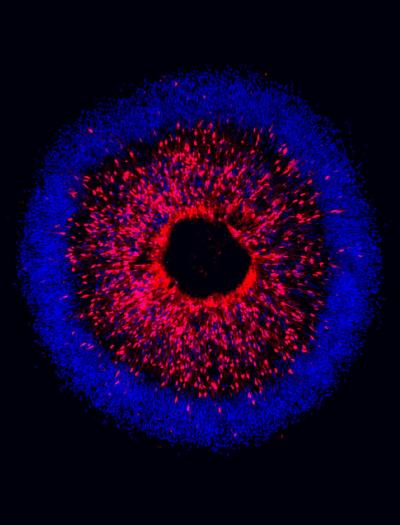

Image credit: IU School of Medicine

The study focused on targeting genetic mutations within retinal ganglion cells, which serve as the connection between the eye and the brain. Researchers found that when differentiating pluripotent human stem cells into retinal ganglion cells, they were able to identify characteristics associated with neurodegeneration in glaucoma.